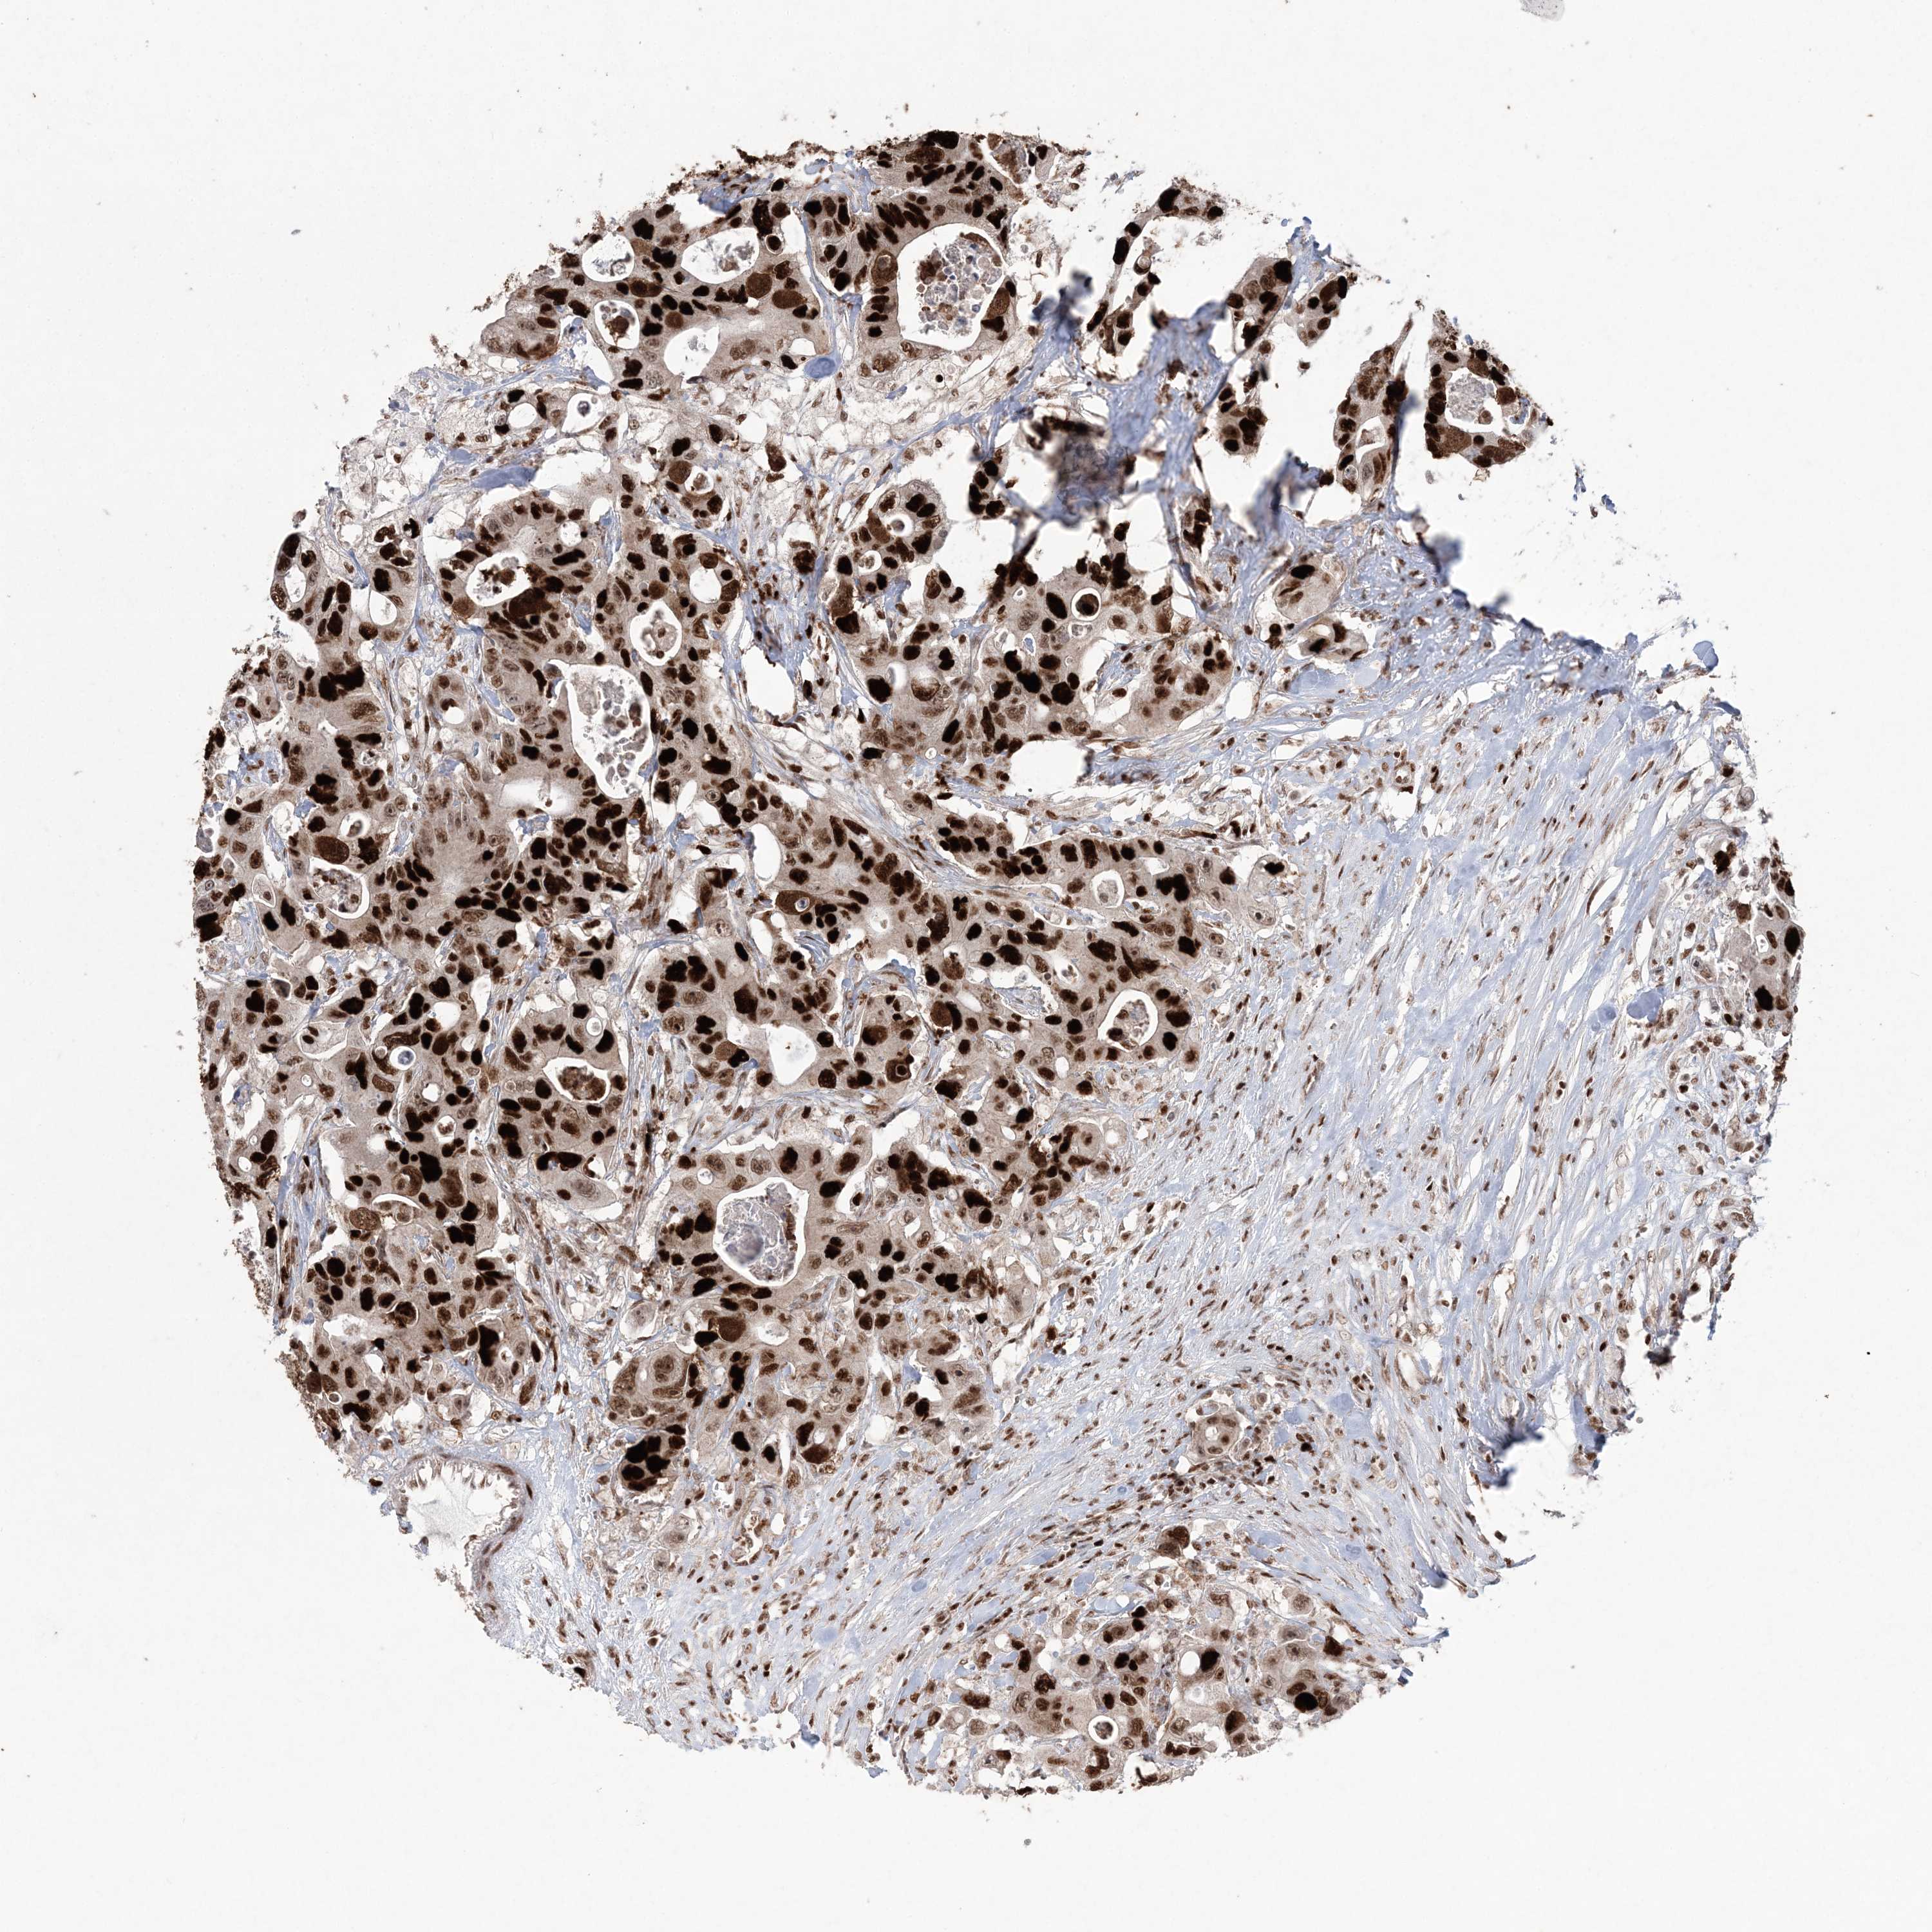

CANCER COLORECTAL CANCER Show tissue menu

COAD TCGA COAD VALIDATION READ TCGA READ VALIDATION PROTEIN COAD CPTAC PROTEIN EXPRESSION

Colorectal cancer

Human cancer

Colon adenocarcinoma